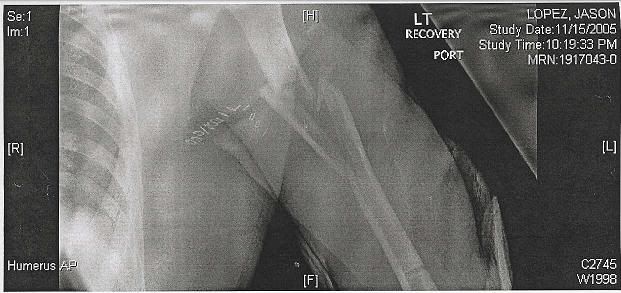

I was in a motorcycle accident 15 months ago.

Injuries:

Compound fracture of my femur - bone shot through my leather suit, split the knuckle on the femur in the knee in half

Shattered my forearm/humerus

Ripped my arm off of my body and was held on by the skin only - all nerves were severed, rendering the arm useless

Tore the brachial artery into my arm - required 16bags of blood (2 full transfusions) over 12 hrs. - died of blood loss and had to be revived

Cracked scapula

Fractured 4 vertebrae

Collapsed lung

Concussion